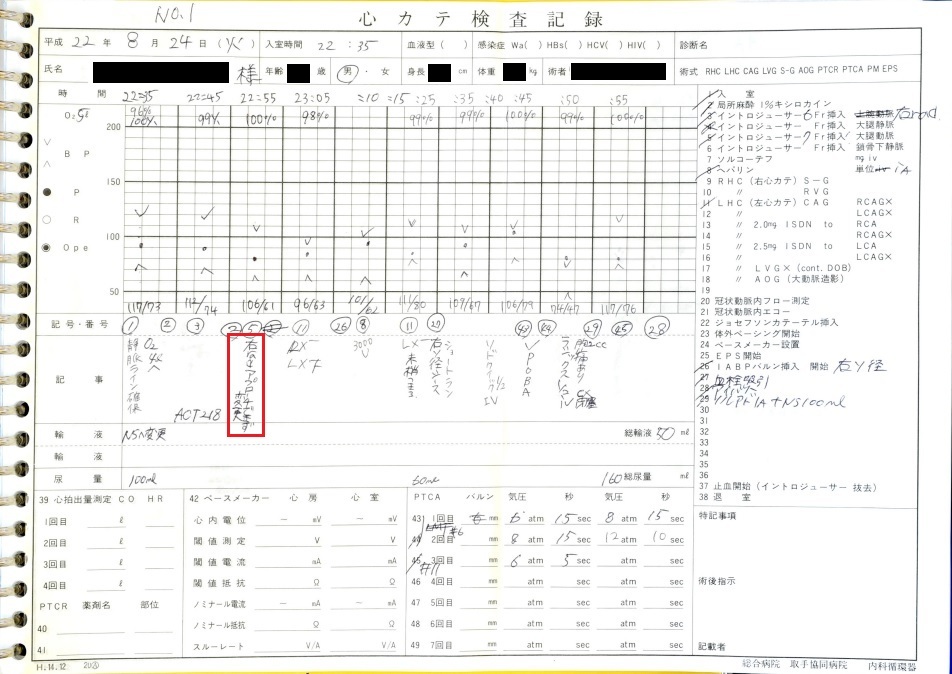

カテーテル治療は22時35分に開始され、右橈骨動脈を穿刺し開始されたが冠動脈へのアプローチに失敗し、右大腿動脈からやり直しとなっている。

証拠: 下記レポートに「右raアプローチできず変更」の記載あり。「ra」とはradial(橈骨動脈)のこと。

動画の記録は23時02分より開始(カテーテル手技開始から27分間のブランクあり)。カテーテル手技開始後、右橈骨動脈から冠動脈へのアプローチ失敗の動画が存在しない。大事故のため、抜き取られた可能性がある。

証拠:PCI動画の更新時間:最初の動画が23:02となっており、それ以前の27分間の動画が存在しない。

心カテ検査記録によると、PCIでの放射線被曝量は10350mGyに達し、許容量を大幅に超過。

証拠:PCIレポート

22時35分に開始され、右橈骨動脈にガイドワイヤーを挿入して手技が開始されたが、 冠動脈にアプローチできず、右大腿動脈から挿入された。その間、アプローチが失敗した時間帯のPCI画像が 存在せず、ここで大事故を起こした証拠であるこの間の画像が抜き取られた可能性が疑われる。 PCIは3時間と長時間を要し、その間の放射線被曝量も人体に深刻な影響を与えるほど大量であった。 PCIの動画を確認すると左冠動脈主幹部閉塞・損傷・解離、左冠動脈前下行枝近位部・遠位部の穿孔、 左回旋枝への血栓閉塞など多数の致命的な手技ミスが認められた。 救命のためには心臓血管外科での開胸手術が必要のはずであったが、医師はPCI終了後、遺族に対して「治療は無事成功した」としてこの手技ミスを隠蔽し、心臓血管外科への手配をせずに放置し談笑していた。